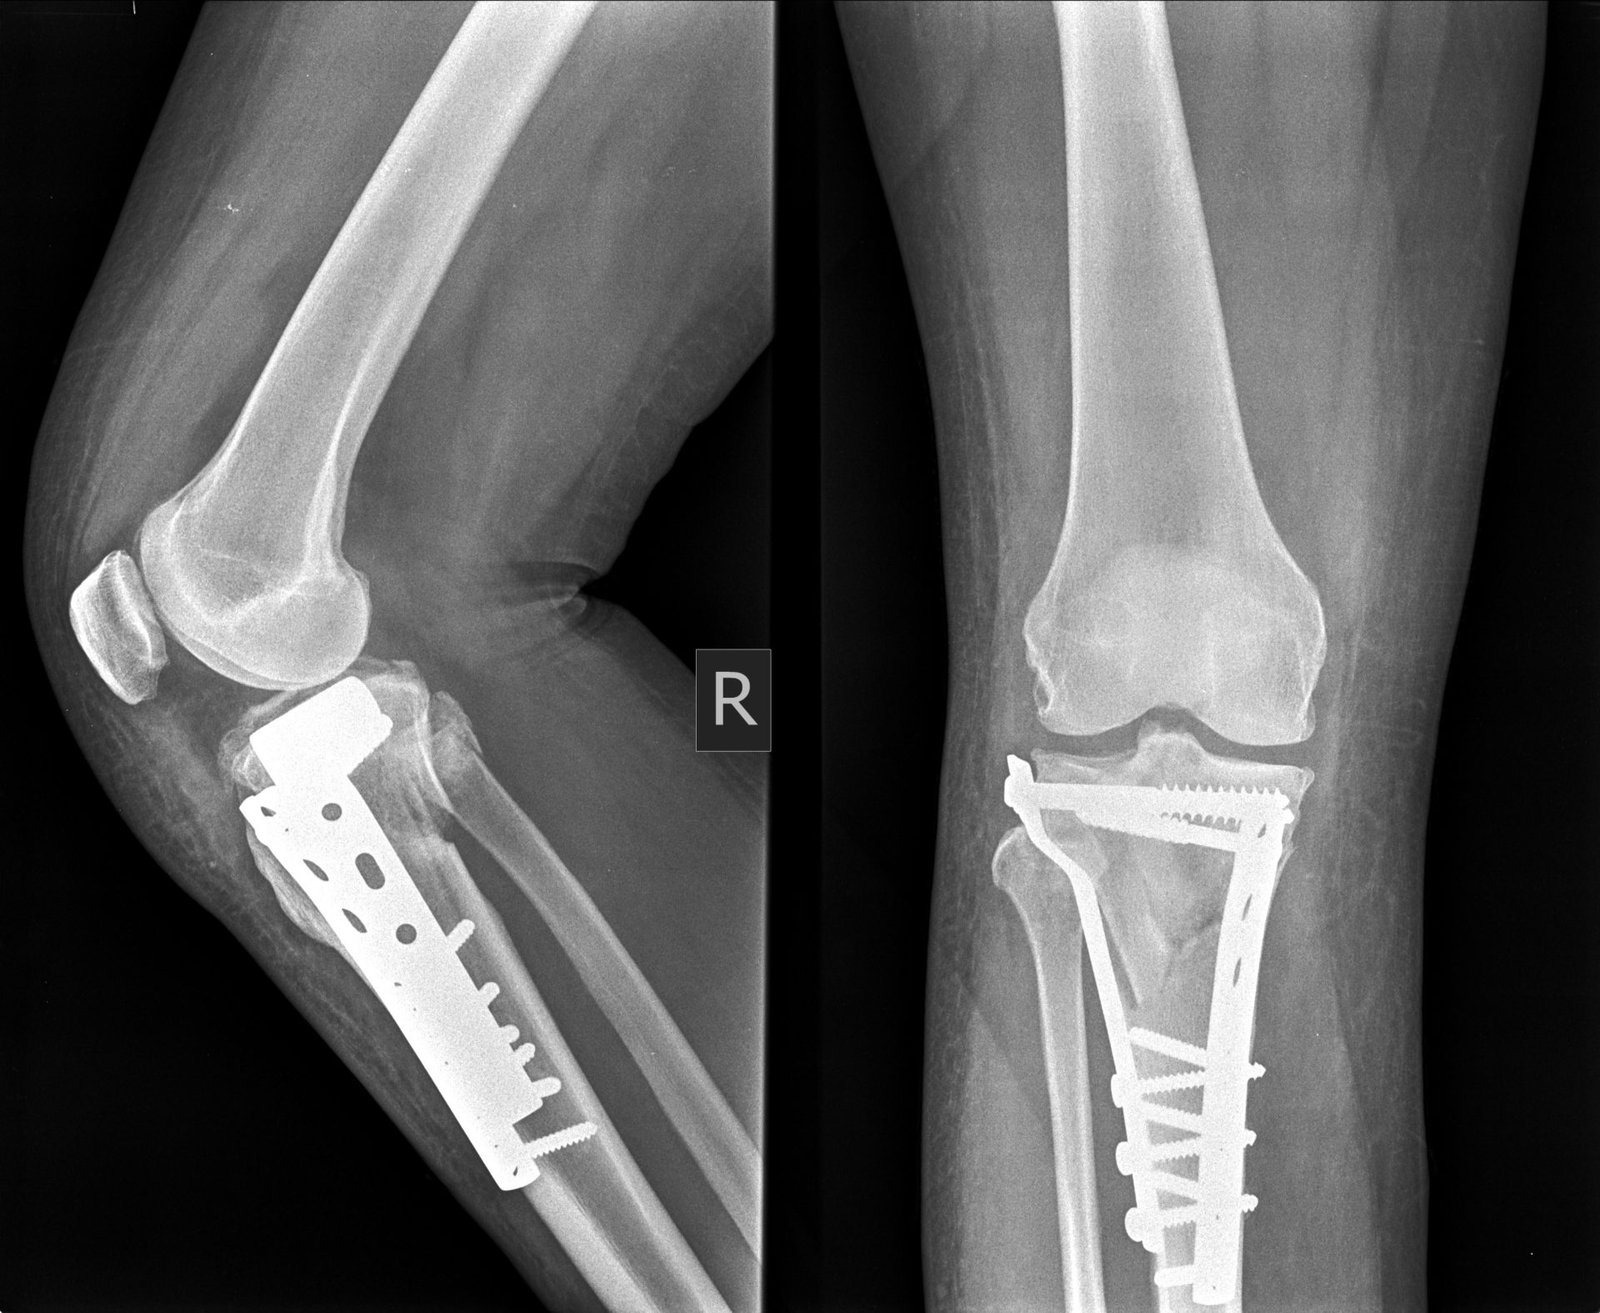

Internal Fixations

Internal fixation is a method which can be used to compress two bony fragments (the technique is then called a leg screw) or a plate to the bone. When a fracture cab be -educed precisely a leg screw may be used to compress the fragments together to provide absolute stability.

Internal fixation is the method s of holding the bone fragment in correct position by using plate, screw and nail.

Methods of internal fixations:

1. Plate and screw.

2. Intramedullary nailing

3. Compression screw – plate.

4. Combined Nail and plate.

5. Transfixation screws.

6. Circumferential wires or bands.

7. Sutures through soft tissues.